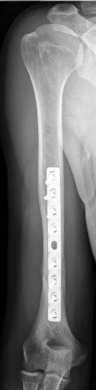

Picture: An upper arm shaft fracture can alternatively be stabilized by a plate that bridges the fracture. The picture shows a shaft fracture with a bending wedge. After surgical treatment, the upper arm shaft is back in the correct axis.